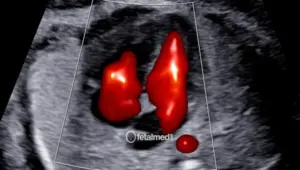

• Coração — quatro câmaras, vias de saída, septo interventricular

O ultrassom morfológico de segundo trimestre é o exame mais completo para avaliação da anatomia fetal. Realizado idealmente entre 20 e 24 semanas de gestação, ele permite visualizar todos os órgãos e sistemas do bebê com alto nível de detalhamento.

É considerado o exame de referência para detecção de malformações fetais e para o planejamento obstétrico da segunda metade da gestação.